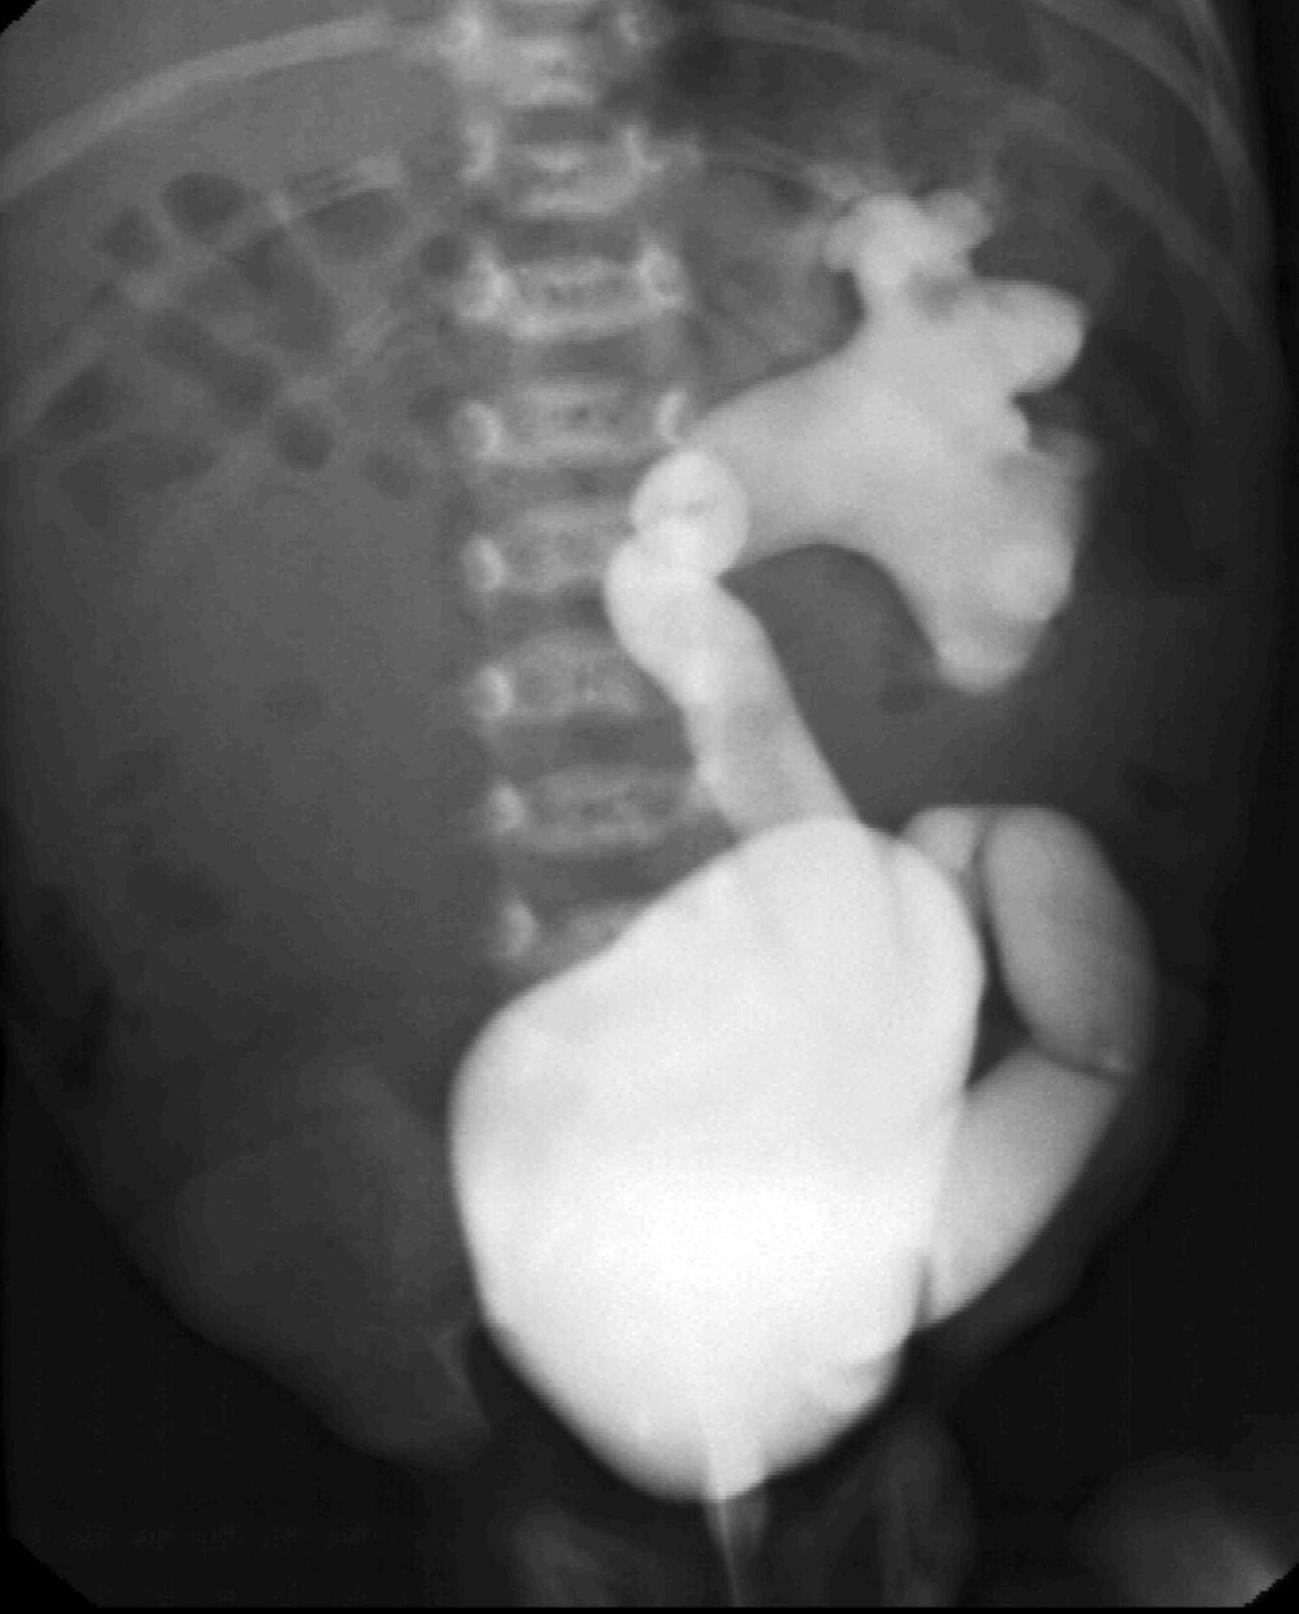

During X-ray examination the contrast material does not progress to the jejunal loops or it shows a “corkscrew” sign on the right side of the vertebrae as it piles up in the twisted intestinal loops.

15. Contrast material empties the stomach slowly, small intestines are found on the right side of the abdomen. Malrotation-volvulus.